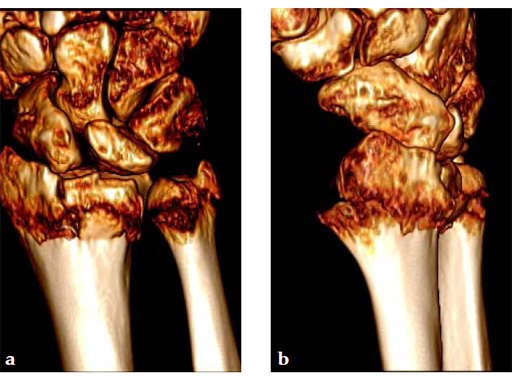

Case 1: A 62-year-old man fell on his outstretched left hand while playing tennis, sustaining an intraarticular fracture of the distal radius, Mller AO Classification 23-C3.2.

Case provided by Renato Fricker, Bruderholz, Switzerland